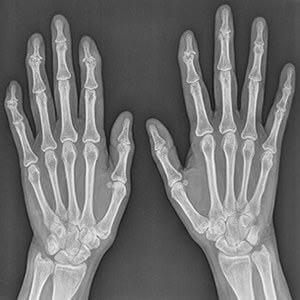

At Baja Hand Clinic, we are dedicated exclusively to the treatment of problems affecting the upper limb, specifically the wrist, hand and fingers, whether traumatic or degenerative